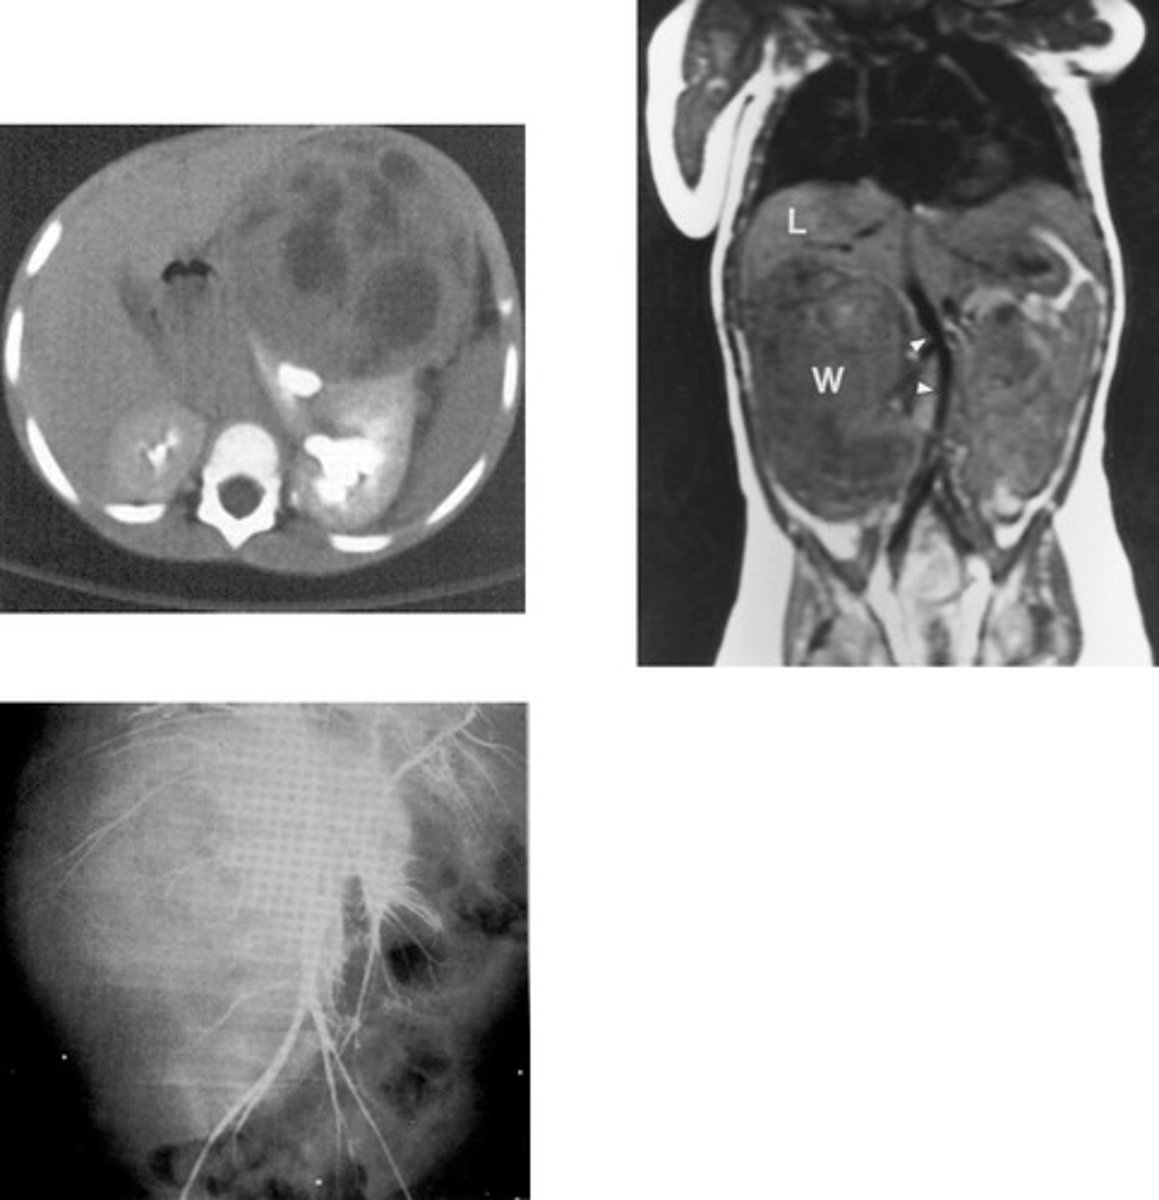

- Renal Cyst

- U/S and CT

- What are fluid filled sacs that forms on/in the kindey, displaces the calyces as it grows, may be single/multiple, and vary in size?

- What imaging modalities are used to diagnose this pathology?

- Polycystic Renal Disease

- 1/3

- 10%

- 30 years

- No

- "Swiss Cheese"

- What is the inherited disorder in which multiple cysts cause lobulated kidney enlargements and renal impairment?